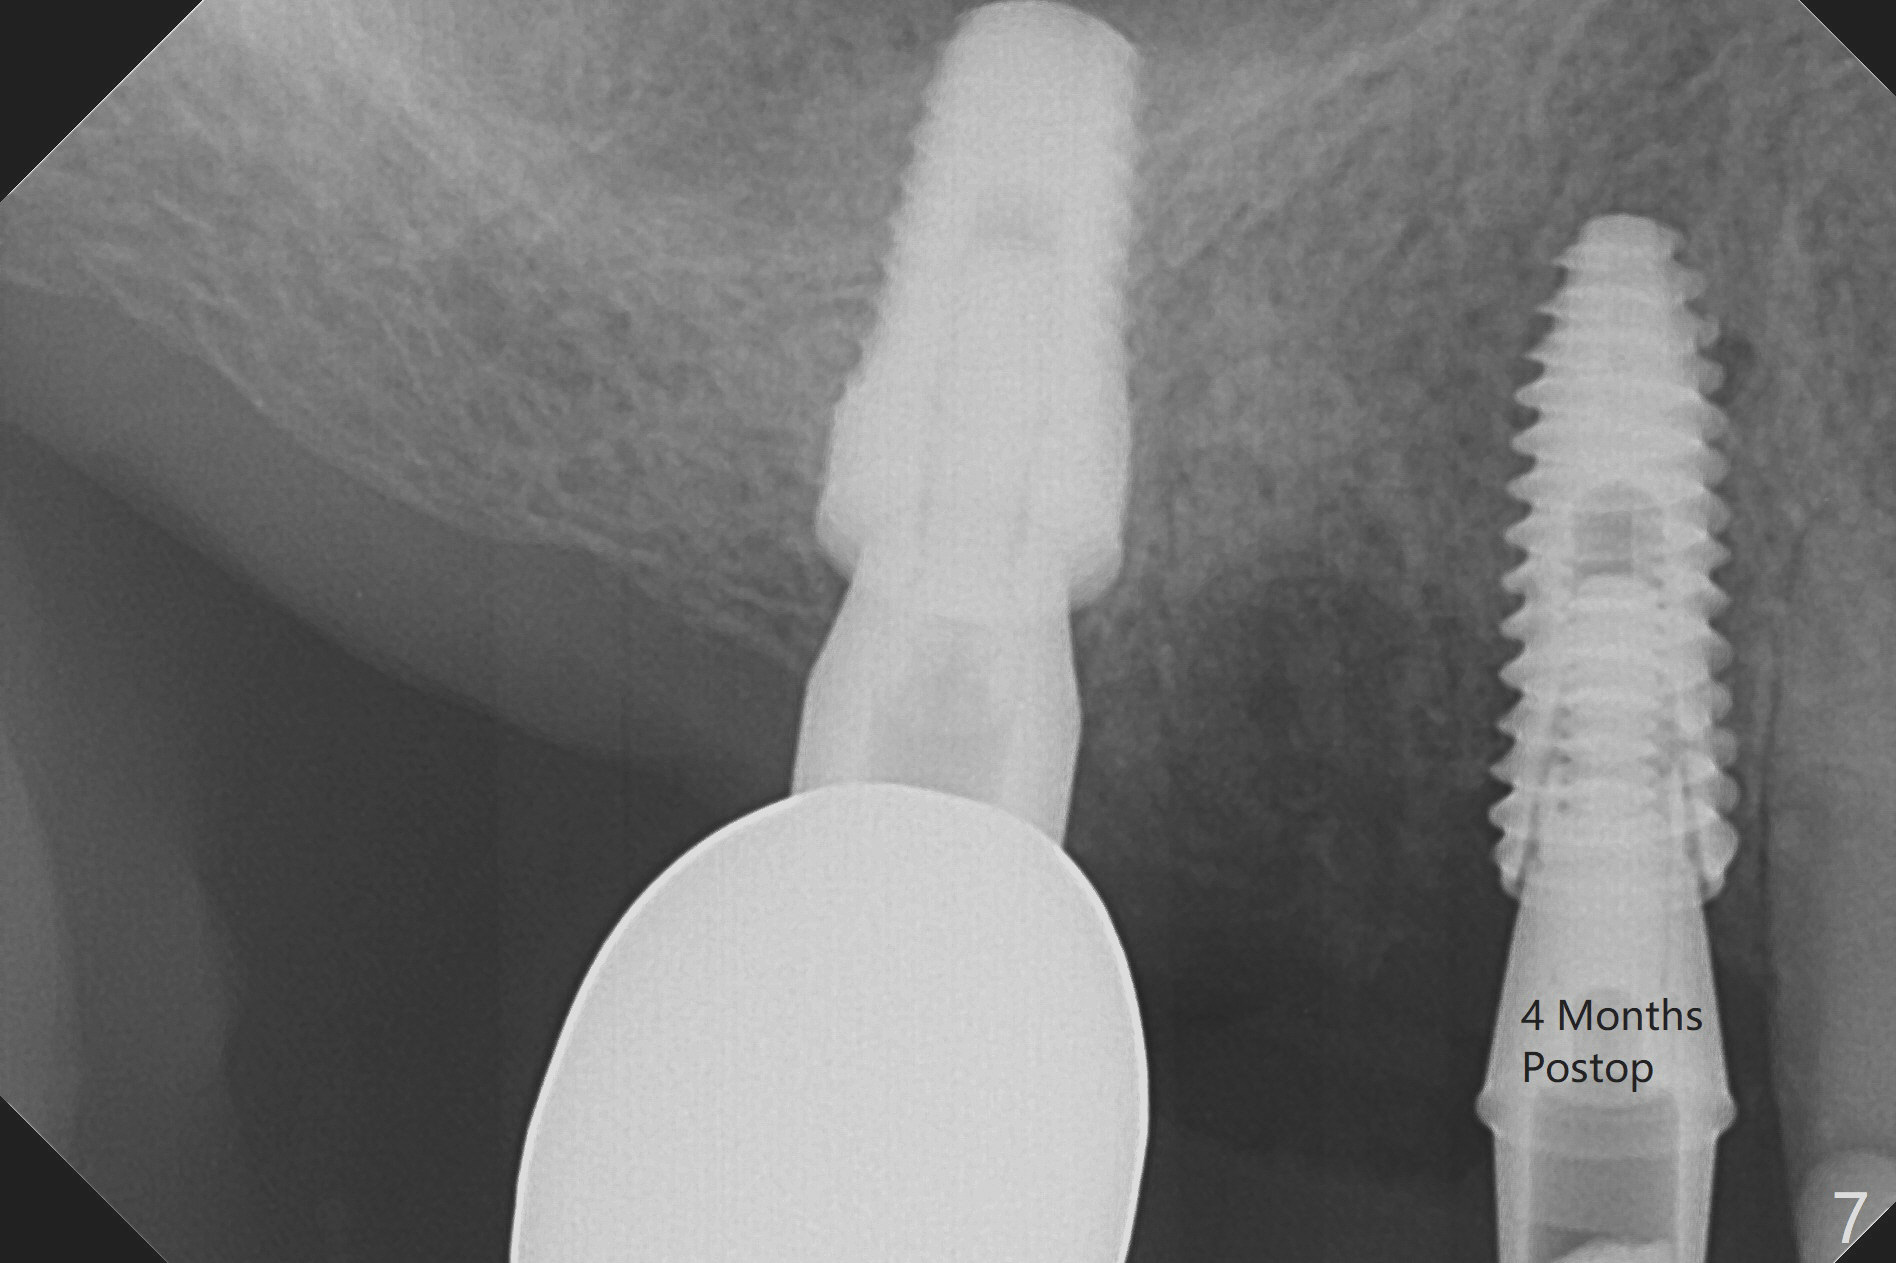

Today schedule is to extract the teeth #4 and 5 and place an implant at #5. When the latter is done, it appears that the implant at #15 should be placed at the same appointment (Fig.1). Once an abutment is placed at #5 (Fig.2 A, 5) for temporary crown (Fig.4 T) , the guide may be not seated again unless the crown is removed. Luckily the implant placement at #15 is quick and smooth with the guide (Fig.3,6). The implants seem to be covered by the bone 4 months postop (Fig.7,8). #15 abutment screw needs retightening because of long crown 1.5 months post cementation. Access hole is palatal. There is premature contact in lateral movement. The buccolingual occlusal table is large at #14 and 15. In fact there is more occlusal contact at #14 than #15 in centric occlusion. Tissue level implants should have been placed to reduce implant/abutment loosening. The incomplete abutment seating (Fig.5,7) is noted after retightening the loose cantilever FPD 1 year post cementation (Fig.9 <). After removal of the FPD, the abutment is reseated completely without interference of the proximal contacts (Fig.10).